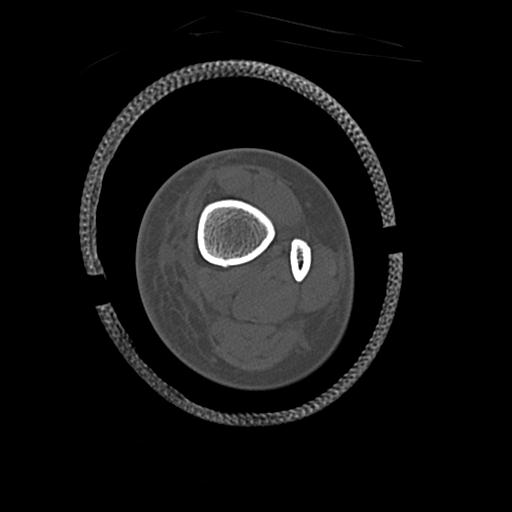

91983 11/16 左膝 2R 11/18 2R 55歳男性 脛骨骨切り術